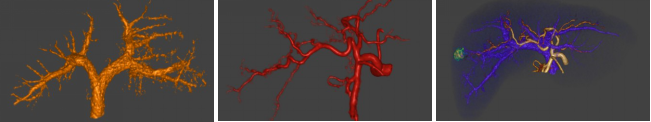

病例三 男,66歲, 突發(fā)頭痛30分鐘, 顱內(nèi)多發(fā)小動(dòng)脈瘤。

CT平掃可見(jiàn)顱內(nèi)左側(cè)小腦區(qū)有環(huán)形高密度影,CTA- MIP中顯示左小腦后下動(dòng)脈瘤, 直徑 約3 mm(黃箭頭所指)

VR圖像中清晰可見(jiàn)前交通動(dòng)脈處小動(dòng)脈瘤1直徑約2mm(紅箭頭所指)

有文章指出, 減影容積CT血管成像對(duì)于檢測(cè)腦動(dòng)脈瘤(3 - 8 mm)的敏感性: 大于8毫米為95 . 6 %左右, 而對(duì)于小于3毫米的微動(dòng)脈瘤卻很容易漏診。

640層寬體探測(cè)器CT擁有0 . 5 mm層厚的探測(cè)器單元, 對(duì)于細(xì)小的病變能夠清晰顯示,大大提高了對(duì)微動(dòng)脈瘤的檢出率。